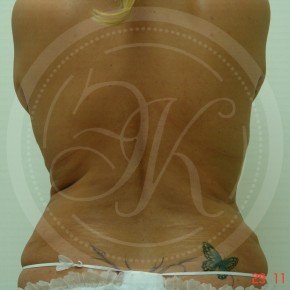

Фото до и после липосакции

В этой галерее мы публикуем снимки тех пациентов, которым была проведена липосакция. Фото до и после в полной мере позволяют оценить результат. Для каждого пациента мы подбираем тот вид вмешательства, который даст лучший результат при минимальном травматизме.